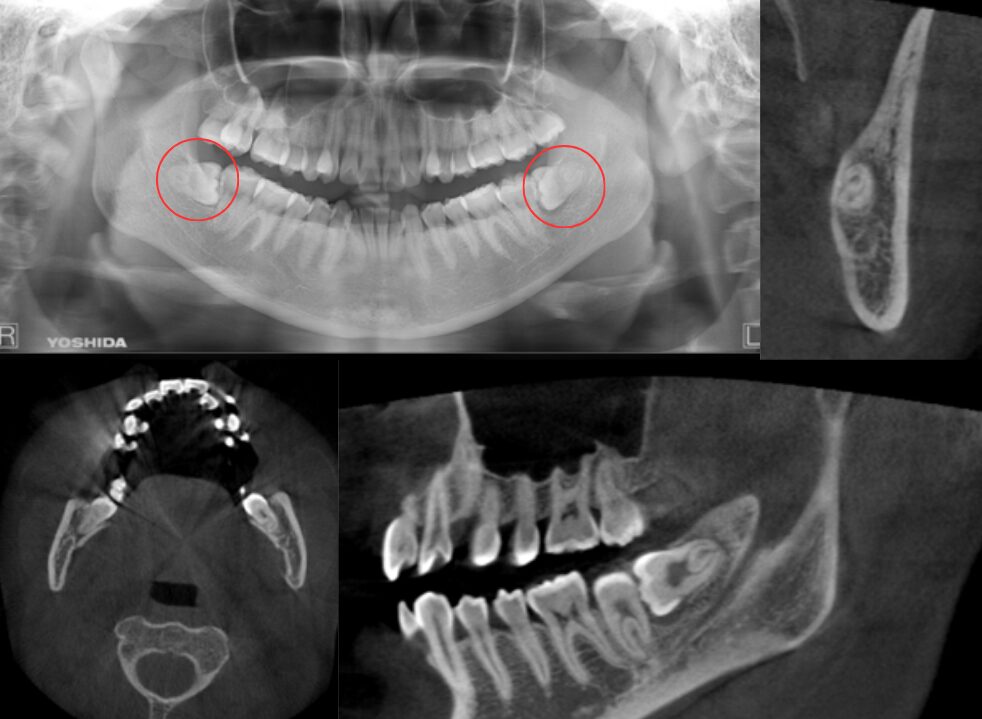

冠状断にて2根、矢状断にて下顎枝から歯冠は露出している症例

| 患者情報 | 26歳 女性 |

| 手術時間 | 15分 |

| 治療内容 | 親知らず抜歯 |

| グレゴリー分類 | クラスⅠ position B |